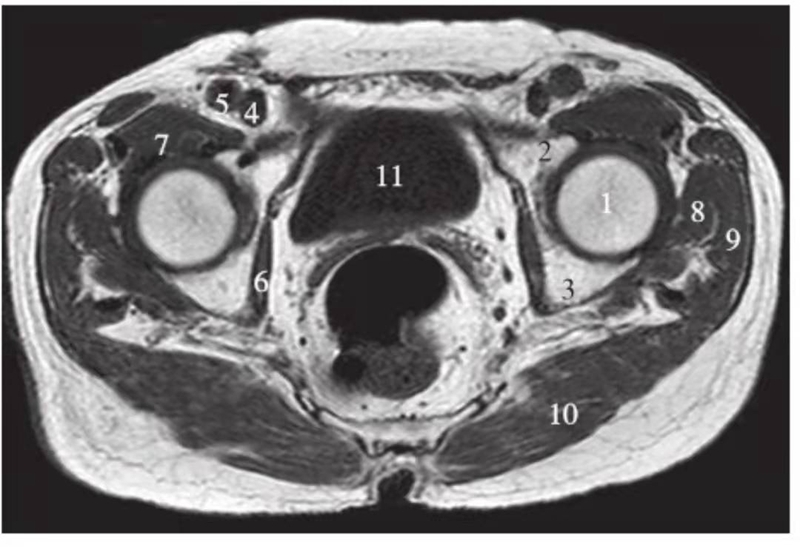

横轴位

正常髋关节经股骨颈层面T1WI像

1.股骨头;2.股骨颈;3.转子间部;4.髋臼后唇;5.耻骨联合;6.髂腰肌;7.闭孔内肌;8.臀大肌